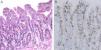

El estudio de autoinmunidad detectó la presencia de anticuerpos antiislotes pancreáticos (ICA: 20 unidades JDF), antitirosín fosfatasa (IA2: 95,83 U/ml) y antiglutamato descarboxilasa (GAD-65: 78,25 U/ml). Además, se objetivó la existencia de anticuerpos antitransglutaminasa tisular IgA (106 U/ml), antiendomisio IgA (1/640) y antigliadina IgA (53 U/ml). El estudio histológico de la biopsia intestinal mediante endoscopia digestiva alta mostró una atrofia vellositaria parcial tipo 3a de la clasificación de Marsh modificada, confirmando el diagnóstico de enfermedad celíaca (fig. 1). Incidentalmente, se detectó la presencia de un lactobezoar gástrico (fig. 2).

Estudio histopatológico, compatible con el diagnóstico de enfermedad celíaca. A) Mucosa duodenal, con linfocitos intraepiteliales, hiperplasia de criptas y atrofia parcial de vellosidades intestinales (grado 3a de la clasificación de Marsh modificada). B) Análisis inmunohistoquímico que muestra linfocitos intraepiteliales CD3 positivos.